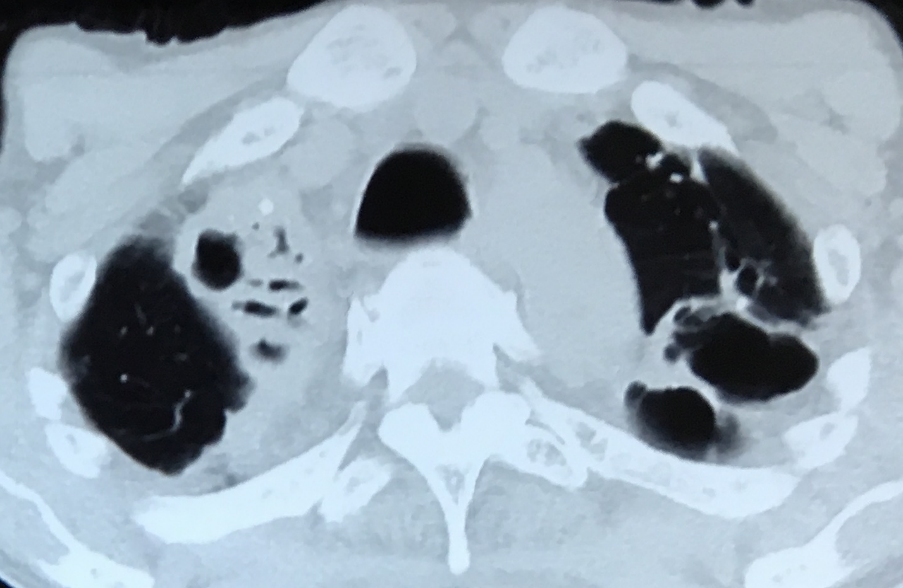

1. 原发性肺结核:主要表现为肺内原发病灶及胸内淋巴结肿大,或单纯的胸内淋巴结肿大。胸内淋巴结环形强化为胸内淋巴结结核相对特征性影像学表现。胸部 CT 可发现纵隔淋巴结肿大,但需与肿瘤淋巴结转移、淋巴瘤、结节病等相鉴别。

*原发性肺结核(胸内淋巴结结核):纵隔淋巴结肿大,增强环形强化为其特征。

*淋巴瘤:纵隔淋巴结肿大(「见缝插针」特征)

*肺结节病:纵隔及双肺门对称性淋巴结肿大,均匀强化